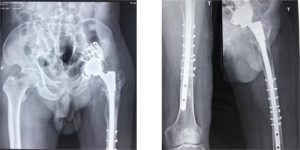

/Uploaded/khds.1cdn.vn/2018/09/16/hinh-anh-khop-duoc-thay-sau-pt-300x150.jpg

Hình ảnh khớp sau thay.

Khi thay khớp, xương ổ cối thưa nên phải dùng rọ đường kính 52mm, chuôi xương đùi dài 360mm, dùng dây thép buộc tăng cường cố định mảnh xương mở cửa sổ. Máu chảy nhiều, BN phải chuyển 750ml.

Sau 4,5 giờ căng thẳng, BN đã được thay khớp có chuôi dài 33cm thành công. Sau 10 ngày BN ra viện trong tình trạng: Không sốt, mạch huyết áp ổn định, tự chống nạng đi lại được, đau nhẹ tại khớp háng, ổ mổ khô, không nóng đỏ, vận động cổ, bàn chân tốt.